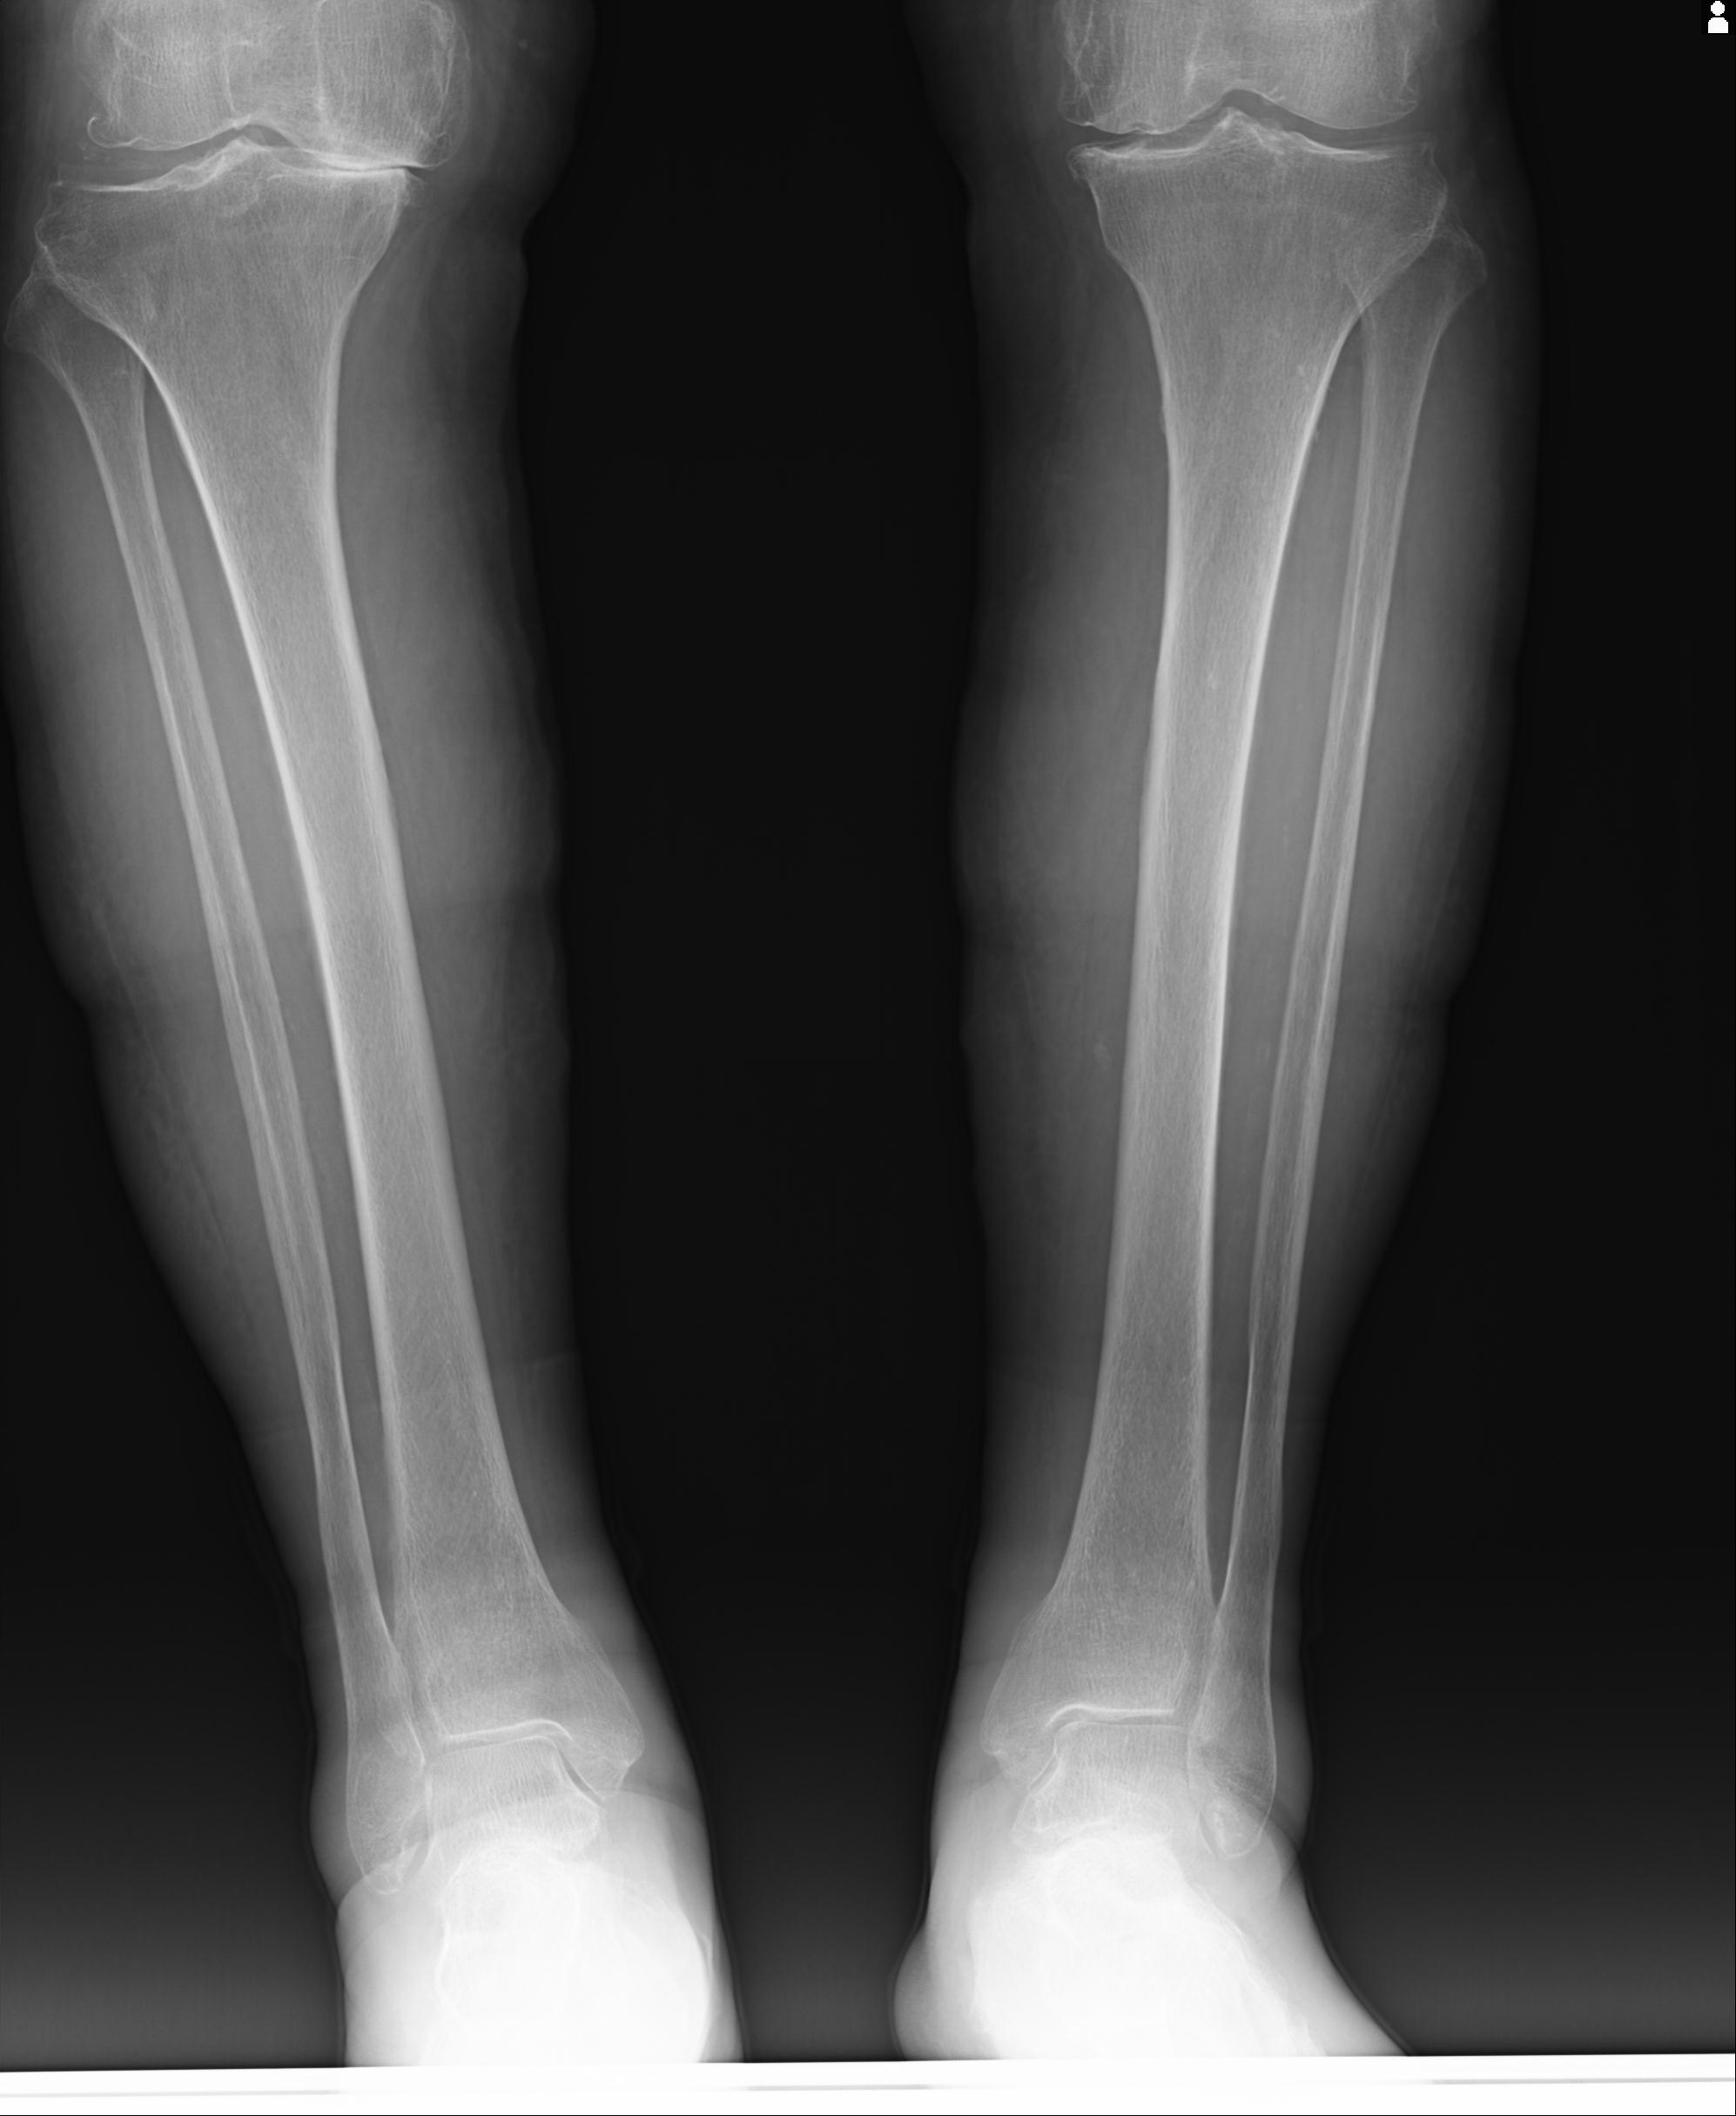

102803 1/12(キウスなし) 1/27 左下腿 4R 30歳女性 左脛骨軸内釘